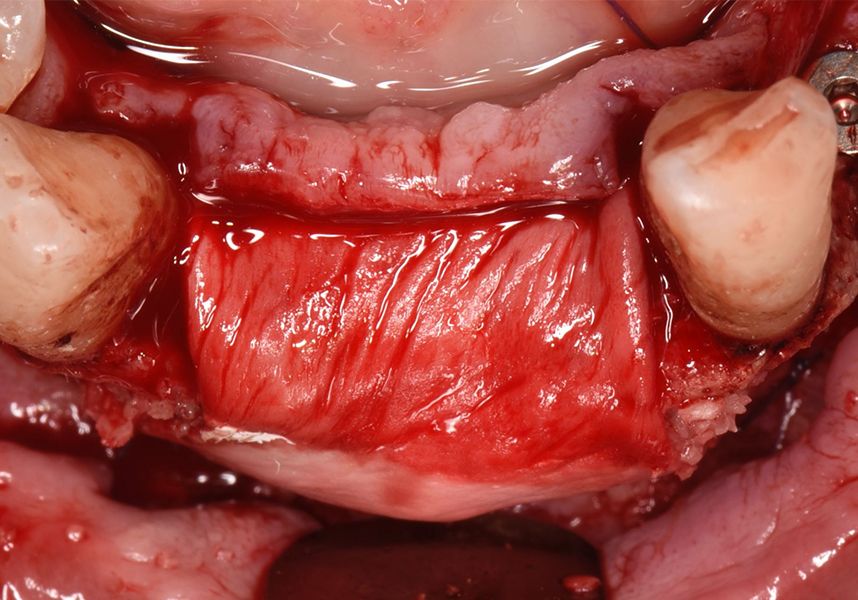

The membrane was sutured with PGA reabsorbable suture to the periosteum to secure it, thus avoiding subsequent reentry to remove fixings such as tacks.

After a post-operative period without complications, the healing abutments were fitted in a second surgical stage 5 months later. Six months after implant placement, the final metal-ceramic prosthetic restoration was loaded.